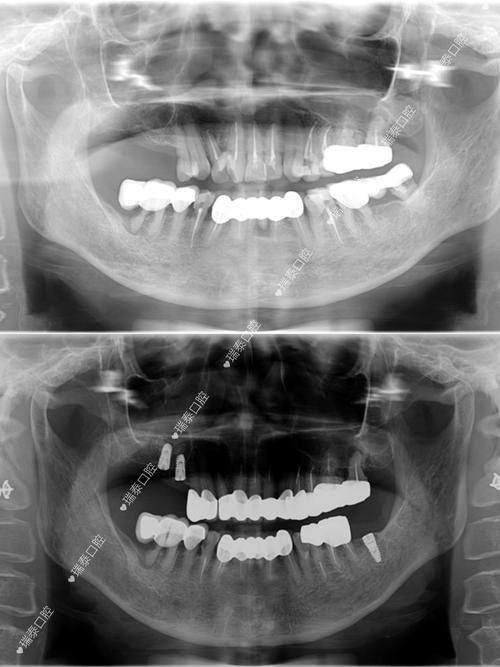

常州新思维口腔门诊部也在这份排名之中,其钛合金种植牙价格为10010元一颗起,种植科主事医师薛寒从业10余年,擅长全口种植牙、以色列科特斯cortex种植牙、韩国sg种植牙、钛合金种植牙等。